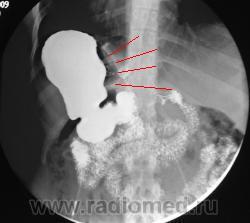

подсказка )))

М.б. в этом месте( стрелка с названием- подсказка) свищь или спайка?

Предлагаю ознакомиться с этими картинками; они многое пояснят! Но, в моём наблюдении не просто ятрогения, но есть осложнение, постарайтесь логически догадаться какое.

Получается муфта соскользнула с желудка и уперлась в диафрагму, тем самым наверное поддавив абдоминальный сегмент пищевода

???? А вернее была наложено выше!

Да, в настоящее время считается одним из самых эффективных методов. Показан пациентам с 3ей и 4ой степенью ожирения. Принцип простой; на проксимальный сегмент желудка накидывается манжетка; которая как петля захватывает желудок; как бы создавая искусственный стеноз на уровне петли и формируя из верхней части маленький резервуар. Этот резервуар быстро наполняется малым количеством пищи; и пациент чувствует насыщение. Люди за год теряют до 30-40 кг. При помощи зонда и имплантированного под кожу аппликатора с физиологическим раствором, можно контролировать степень сужения (диаметра петли). Одно из самых распространённых осложнений при таких процедурах - синдром "соскальзывания" петли. Slipped gastric band syndrome.